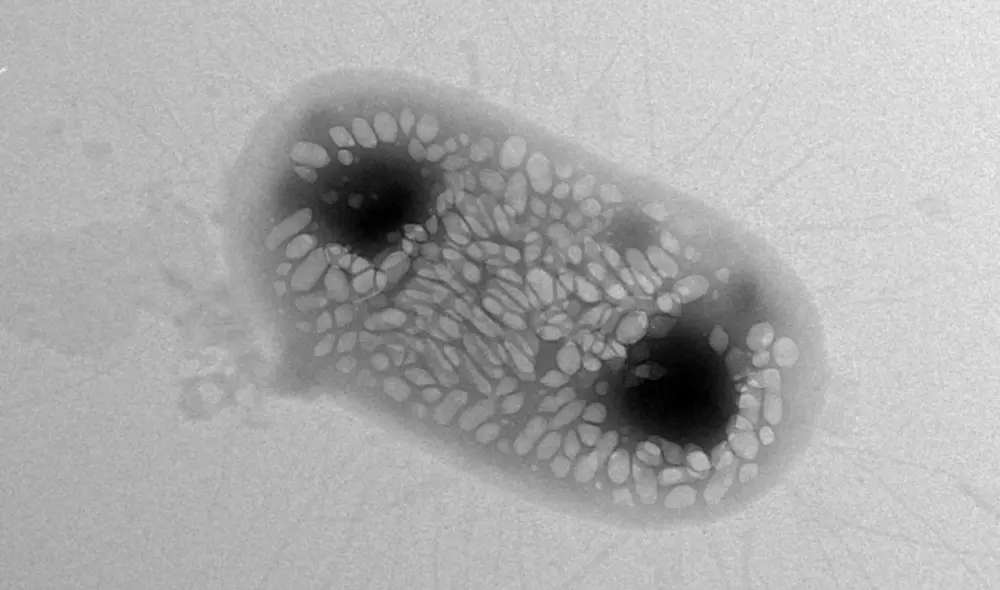

La fabimicina ataca a las bacterias gramnegativas, un grupo de patógenos que son cada vez más difíciles de combatir por los medicamentos. La investigación ha sido publicada en un artículo de la revista ACS Central Science.

Las bacterias gramnegativas están detrás de infecciones en el tracto urinario, los pulmones y el torrente sanguíneo.

Su resistencia a los medicamentos se debe a que poseen una cápsula externa que las protege de sustancias dañinas y también a un mecanismo conocido como bombas de expulsión activas.

Sin embargo, la fabimicina atraviesa la capa externa de la célula y evita que las bombas de expulsión la alejen. De ese modo, la molécula logra acumularse donde puede causar más daño sin eliminar bacterias saludables.